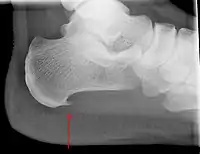

يُعتبر مهماز العقب من الحالات المُكتشفة عرضيًا والمُرتبطة بالتهاب اللفافة الأخمصية، وهو عبارةٌ عن تكلس عظميٍ صغير على العظم العَقِبي، وقد يحدث في حوالي 50% من المُصابين بالتهاب اللفافة الأخمصية.[6] في مثل هذه الحالات، فإنَّ التهاب اللفافة الأخمصية يُؤدي إلى الألم العَقِبي، وليس المهماز نفسه.[18] على الرغم من الأهمية السريرية لمهماز العقِب في حالة التهاب اللفافة الأخمصية، إلا أنَّ سبب حدوث المهماز لا زال غيرَ واضح.[17]

عادةً لا تُوجد حاجةٌ لاستعمال التصوير الطبي، وذلك كونه مكلفًا ولا يُغير عادةً في كيفية التعامل مع التهاب اللفافة الأخمصية.[20] عندما لا يُكون التشخيص ظاهرًا سريريًا، فإنهُ يُوصى بإجراء أشعةٍ سينية جانبية على الكاحل، وذلك بهدف تقييم الأسباب الأُخرى لألم العَقِب مثل كسور الإجهاد أو حدوث مهمازٍ عظمي.[4]